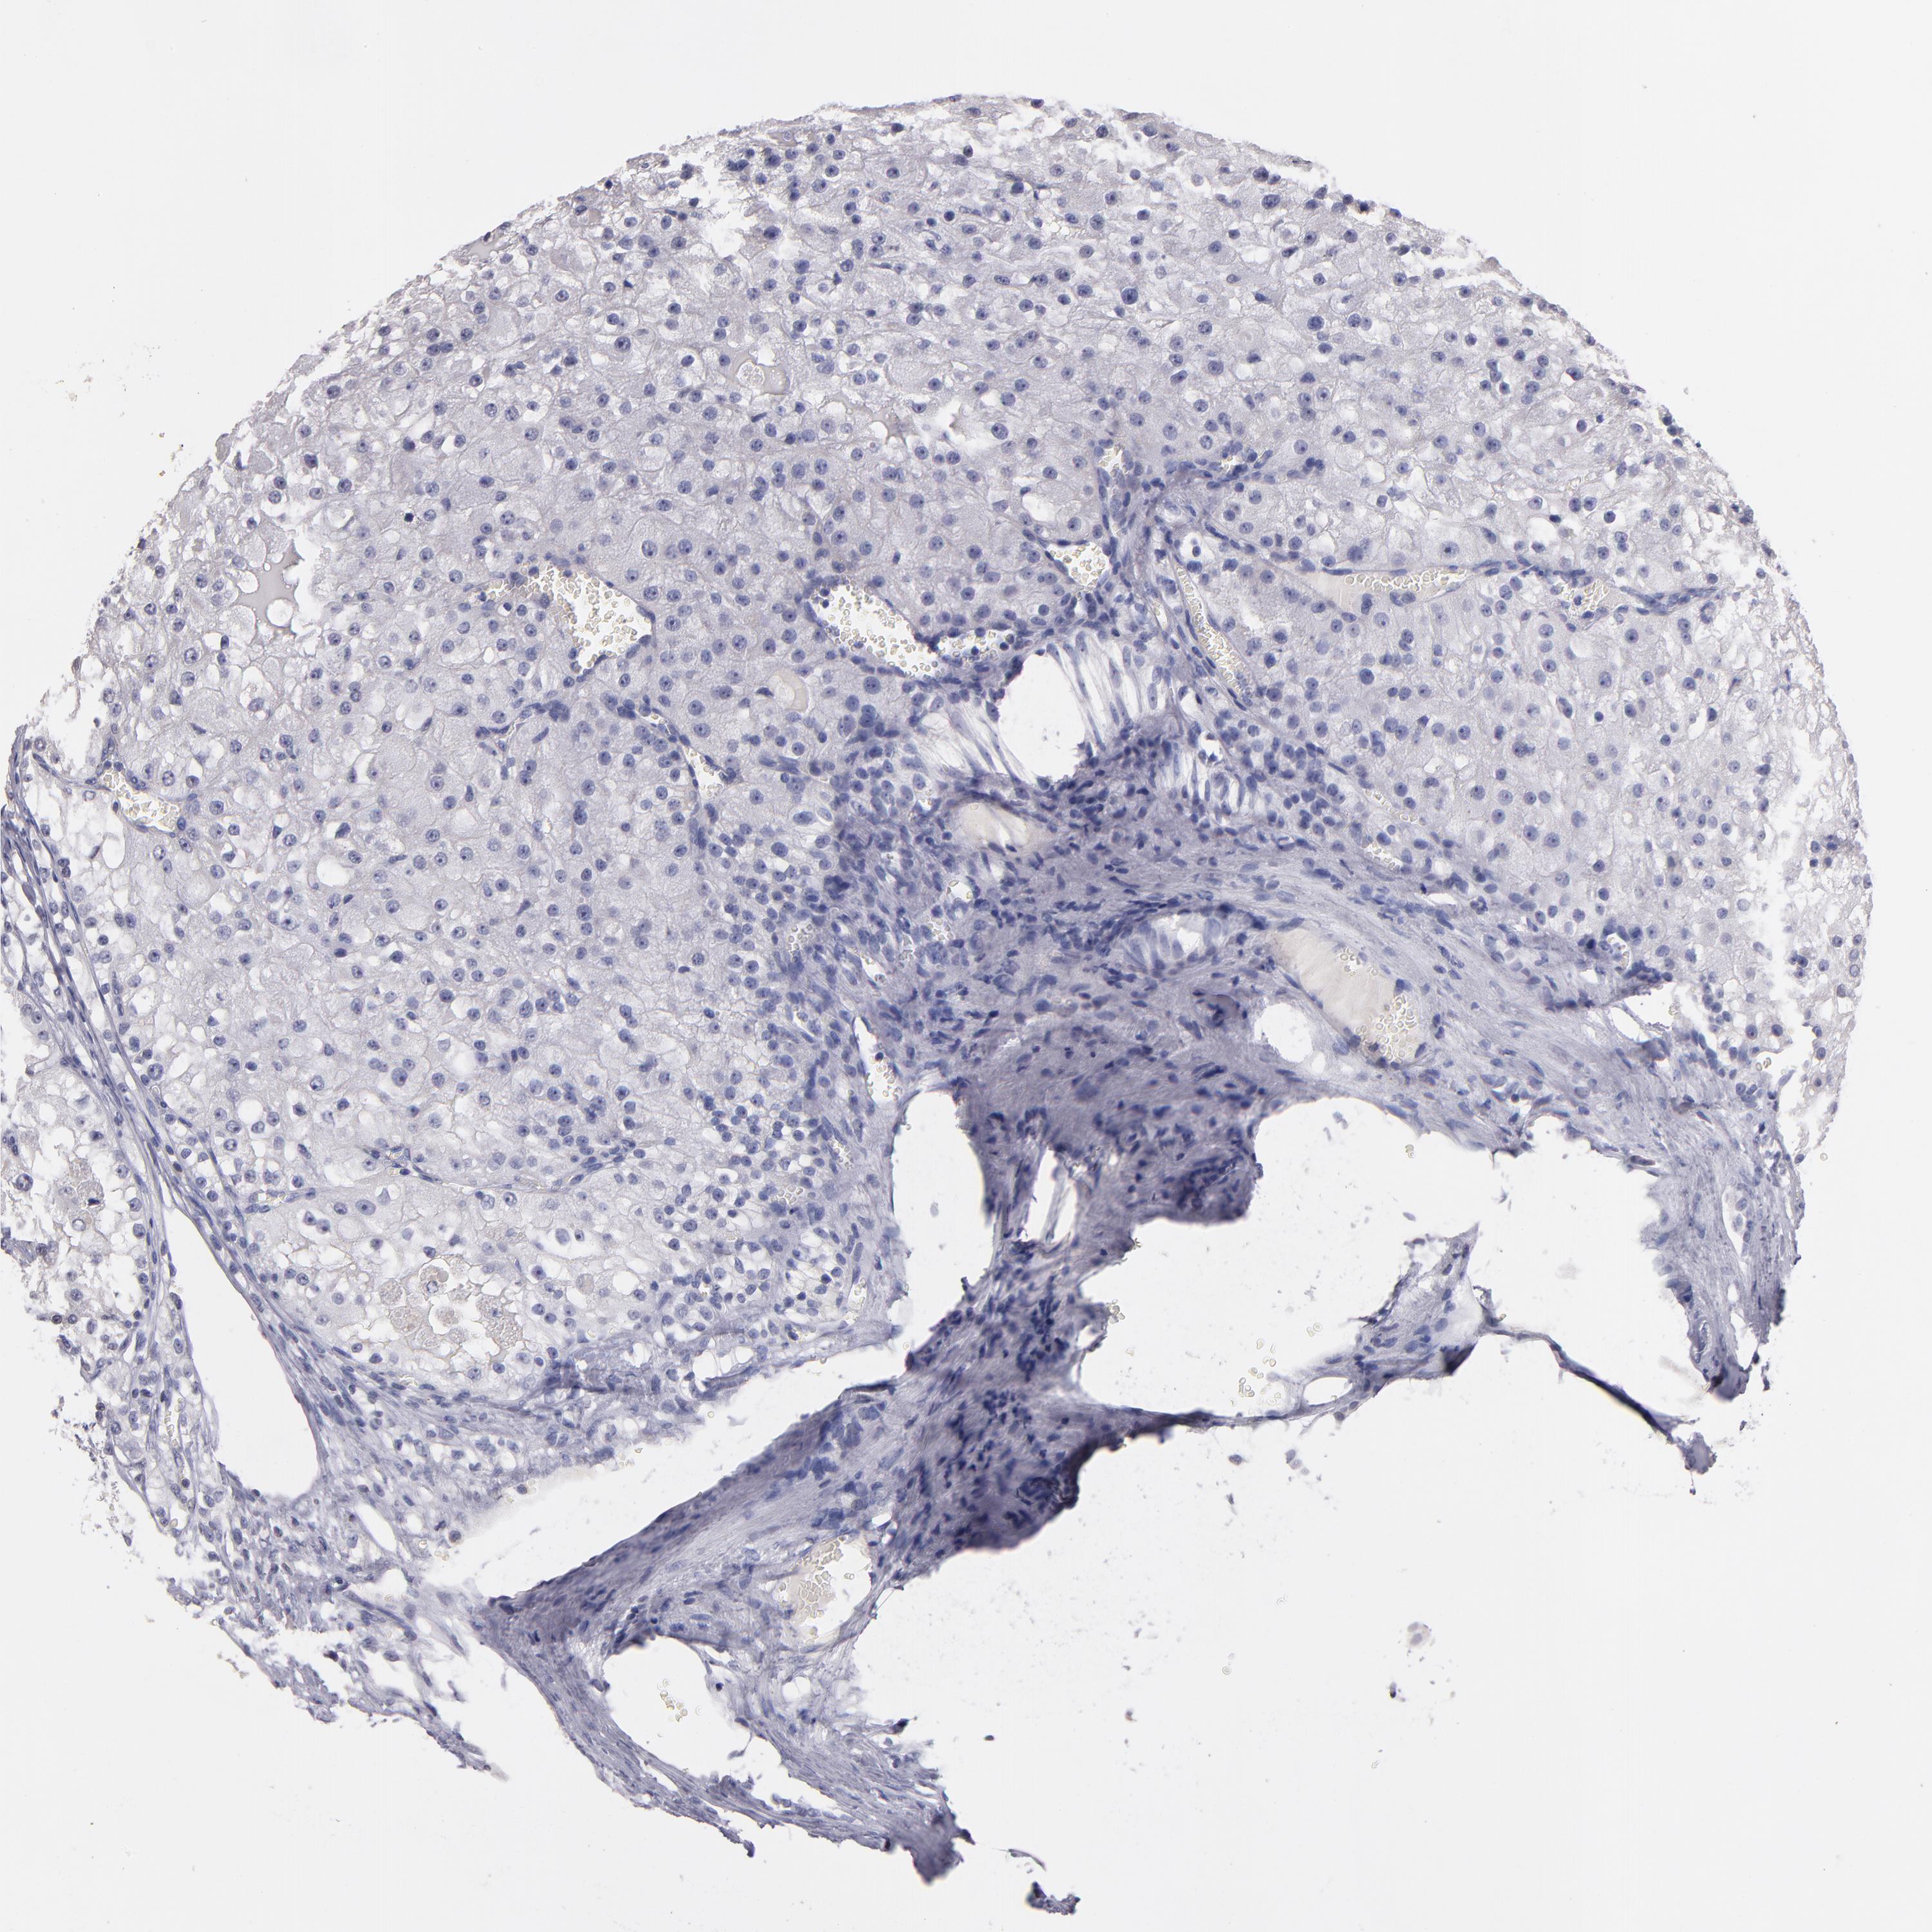

KIDNEY RENAL CLEAR CELL CARCINOMA (VALIDATION) - Interactive survival scatter ploti

The Survival Scatter plot shows the clinical status (i.e. dead or alive) for all individuals in the patient cohort, based on the same data that underlies the corresponding Kaplan-Meier plots. Patients that are alive at last time for follow-up are shown in blue and patients who have died during the study are shown in red.

The x-axis shows the expression levels (FPKM) of the investigated gene in the tumor tissue at the time of diagnosis. The y-axis shows the follow-up time after diagnosis (years). Both axes are complimented with kernel density curves demonstrating the data density over the axes. The top density plot shows the expression levels (FPKM) distribution among dead (red) and alive patients (blue). The right density plot shows the data density of the survived years of dead patients with high and low expression levels respectively, stratified using the cutoff indicated by the vertical dashed line through the Survival Scatter plot. This cutoff is automatically defined based on the FPKM cutoff that minimizes the p-score. The cutoff can be changed by dragging the vertical line or by entering a cutoff value in the square labeled "Current cut-off".

Under the Survival Scatter plot the p-score landscape (black curve; left axis) is shown together with dead median separation (red curve; right axis). Dead median separation is the difference in median mRNA expression between patients who have died with high and low expression, respectively. It is calculated as follows: median FPKM expression of dead patients with high expression - median FPKM expression of dead patients with low expression. This is intended to aid the user in visually exploring custom cutoffs and the associated p-scores and dead median separation.

Individual patient data is displayed and can be filtered by clicking on one or more of the category buttons on the top of the page. Categories describing expression level and patient information include: high, low, alive, dead, female, male and tumor stages. The scale of the x-axis can be toggled between linear and log-scale by clicking on the "x log" button. Mouse-over function shows TCGA ID, patient information and mRNA expression (FPKM) for each patient.

& Survival analysisi

Kaplan-Meier plots summarize results from analysis of correlation between mRNA expression level and patient survival. Patients were divided based on level of expression into one of the two groups "low" (under cut off) or "high" (over cut off). X-axis shows time for survival (years) and y-axis shows the probability of survival, where 1.0 corresponds to 100 percent.

SOX10 is not prognostic in Kidney Renal Clear Cell Carcinoma (validation)

TCGA RNA samplesi

RNA-seq data is reported as average FPKM (number Fragments Per Kilobase of exon per Million reads), generated by the The Cancer Genome Atlas (TCGA) .

Normal distribution across the dataset is visualized with box plots, shown as median and 25th and 75th percentiles. Points are displayed as outliers if they are above or below 1.5 times the interquartile range. FPKM values of the individual samples are presented next to the box plot.

Average pTPM 0.1

Number of samples 100